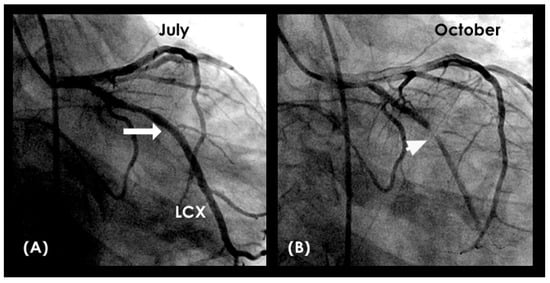

Figure 24.

(A,B) Left coronary artery angiogram. (A) This is the left coronary angiogram with a patent left main (LM) and left circumflex (LCX) artery in a patient. (B) Three months later, a severe lesion in the mid-segment was observed (arrow). Could the physician have predicted the appearance of the severe lesion by reviewing the coronary flow of the July coronary angiogram? (C,D) The blood is seen moving in a proximal-to-distal segment at fast speed of diastole in laminar fashion with a thin boundary layer. (E) The blood flowed further downstream, but only at a minimal distance because this was the beginning of systole.

Figure 25.

(A) The blood flowed further downstream (white arrow); however, there was a marked area with high concentration of contrast at the location transitioning from diastole to systole. This was the location of future lesion 3 months later (white arrowhead). This is the second image of the systole. (B) The high concentration of contrast (white arrowhead) continued at the location while the blood flow continued to flow forward distally (white arrow). This is the 3rd image of the systole. (C) The distal flow moved forward (black arrow, while there is some attenuation of the contrast (white arrow)). The flow looks more disorganized with a large boundary layer. This is the 4th image of the systole.

Figure 26.

(A) The contrast seemed to fade away (white arrowhead) with a thin boundary layer (white arrow). This is the 5th image of the systole. (B) Black contrast is seen moving backward to the proximal left circumflex (white arrow). This was the angiographic evidence of reverse flow. (C) Black contrast is seen more prominently and moves backwards to the proximal left circumflex (white arrow). This is the angiographic evidence of reverse flow (white arrow). In the next 3 images (D–F), there is persistent stagnant contrast at the proximal segment of the LCX. This was the location of future lesion 3 months later (a little distal to the origin of the side-branch).